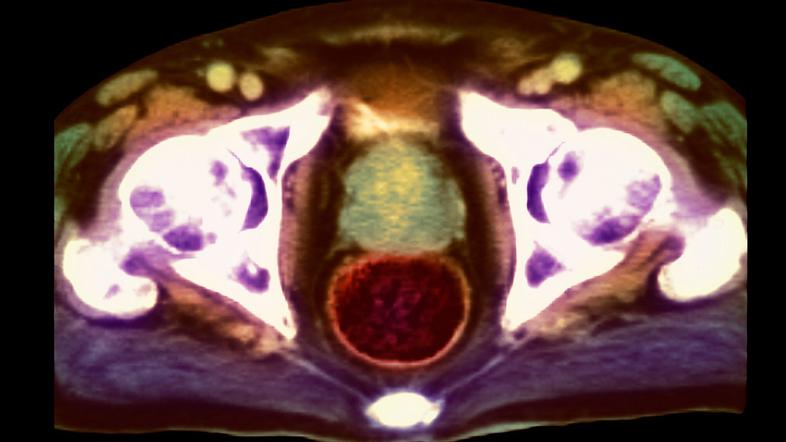

Rak prostate

Rak prostate | Avtor: Profimedia Profimedia

Najpogostejši rak pri moških

Podatki o incidenci raka prostate kažejo, da je to v Sloveniji najpogostejši rak pri moških in drugi najpogostejši rak skupno. "Njegova incidenca je do leta 2011 strmo naraščala, po tem letu pa se je ustalila pri nekaj več kot 1.400 novoodkritih rakov letno," navajajo v poročilu. "Prav tako se je ustalilo število umrlih zaradi raka prostate pri nekaj več kot 350 oseb letno." Podatki so na voljo do leta 2014.